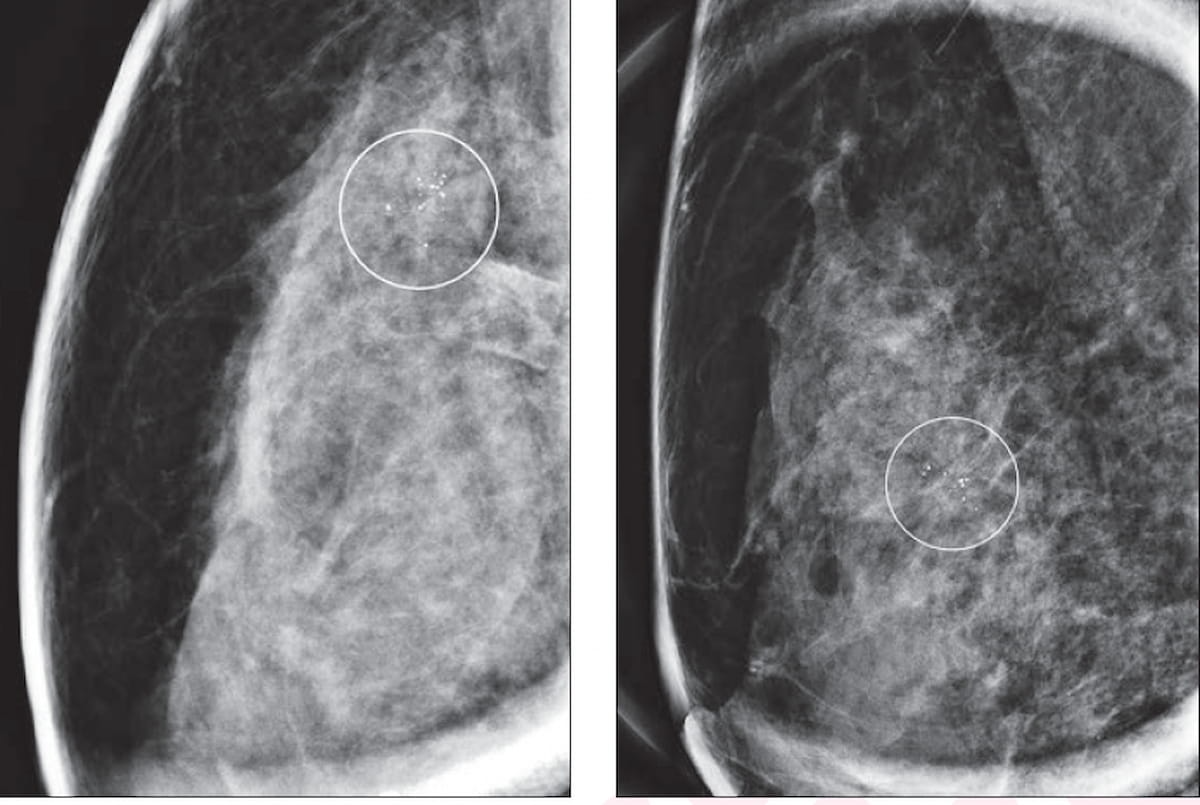

For women with dense breasts, only 25 percent of breast radiologists are confident in the use of mammography for diagnosing invasive lobular carcinoma, according to newly published survey results from the Society of Breast Imaging.

Contrast-enhanced mammography had a 98 percent sensitivity rate for diagnosing invasive lobular carcinoma and provided high conspicuity for 82 percent of detected lesions, according to research presented at the recent Radiological Society of North America (RSNA) conference.